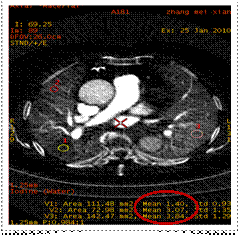

ROI 1(低灌注區(qū)): 碘的物質(zhì)濃度1.40mg/ml

ROI 2(同側(cè)肺對照區(qū))碘的物質(zhì)濃度3.07mg/ml

ROI 3(對側(cè)肺同區(qū)域)碘物質(zhì)濃度 3.84mg/ml

寶石能譜CT開創(chuàng)了CT定量分析的新時代。